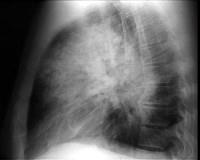

问题 患者输液过程中突发胸闷,气急,咳痰,胸部正侧位片如图,最可能的诊断为 ( )

选项 A.硅沉着病合并感染 B.中央型肺水肿 C.真菌感染 D.间质性肺水肿 E.腺病毒肺炎

答案 B